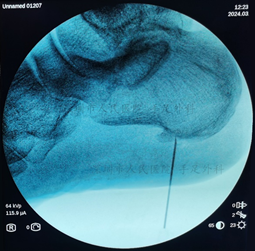

▶一些顽固疼痛的患者经过少应6个月的保守治疗后症状仍持续存在,应考虑手术治疗。

图10:采用关节镜微创技术清理病变组织和增生骨刺,术中定位病变部位

图11:术中X光示骨刺已清除